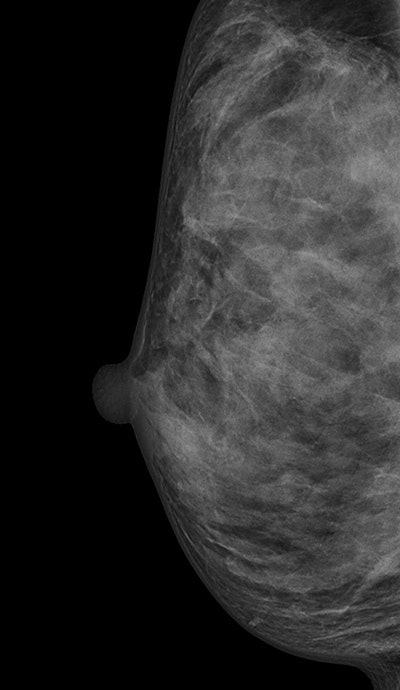

ACR's BI-RADS classifies breasts as almost entirely fatty (ACR 1), scattered areas of fibroglandular density (ACR 2), heterogeneously dense (ACR 3), or extremely dense (ACR 4). Heterogeneously dense and extremely dense are usually combined into one category of dense breasts. They are indicated by quartile ranges of percentage dense tissue more than 50% and as possibly obscuring small masses and lowering the sensitivity of mammography.

Most of the dense breasts are classified as heterogeneously dense and the frequency of breast densities is reported as 10% fatty, 40% scattered, 40% heterogeneously, and 10% extremely dense, the study authors explained. Higher breast density is associated with decreased mammographic sensitivity and specificity, as well as with increased breast cancer risk. Breast density may also be a factor that contributes differentially to screen-detected breast cancers and interval breast cancers, they added.